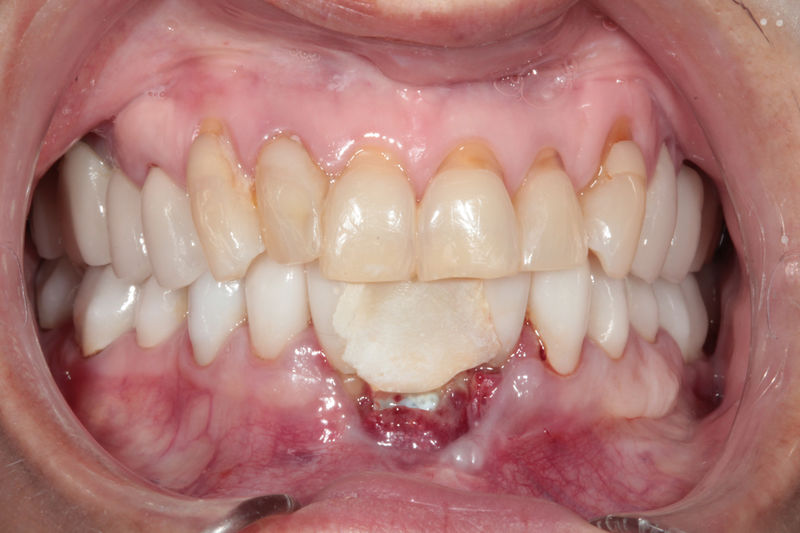

Implante fracasado, extracción, carillas, coronas y prótesis fija.

Cirugía ortognática, implantes, carillas y coronas,